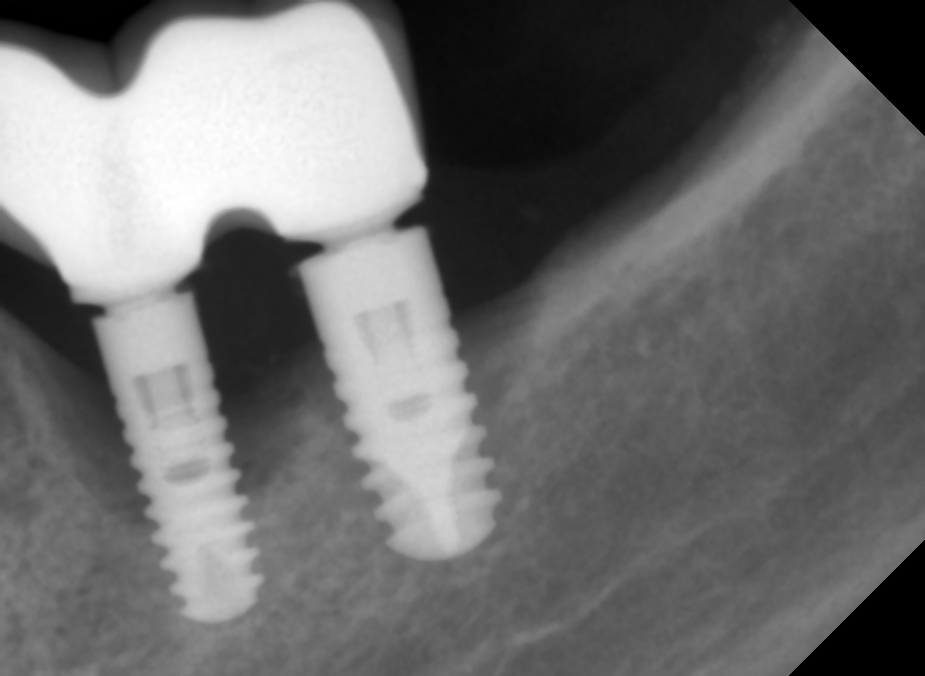

На RG:

Значительная деструкция кости, "костный карман" в области имплантатата на месте пятёрки. Костные пики утрачены.

На рентгенограмме периимплантататит выглядит как деструкция кости вокруг имплантатата, иногда заметен характерный "костный карман". Имплантат частично остаётся в кости, частично находится вне кости.